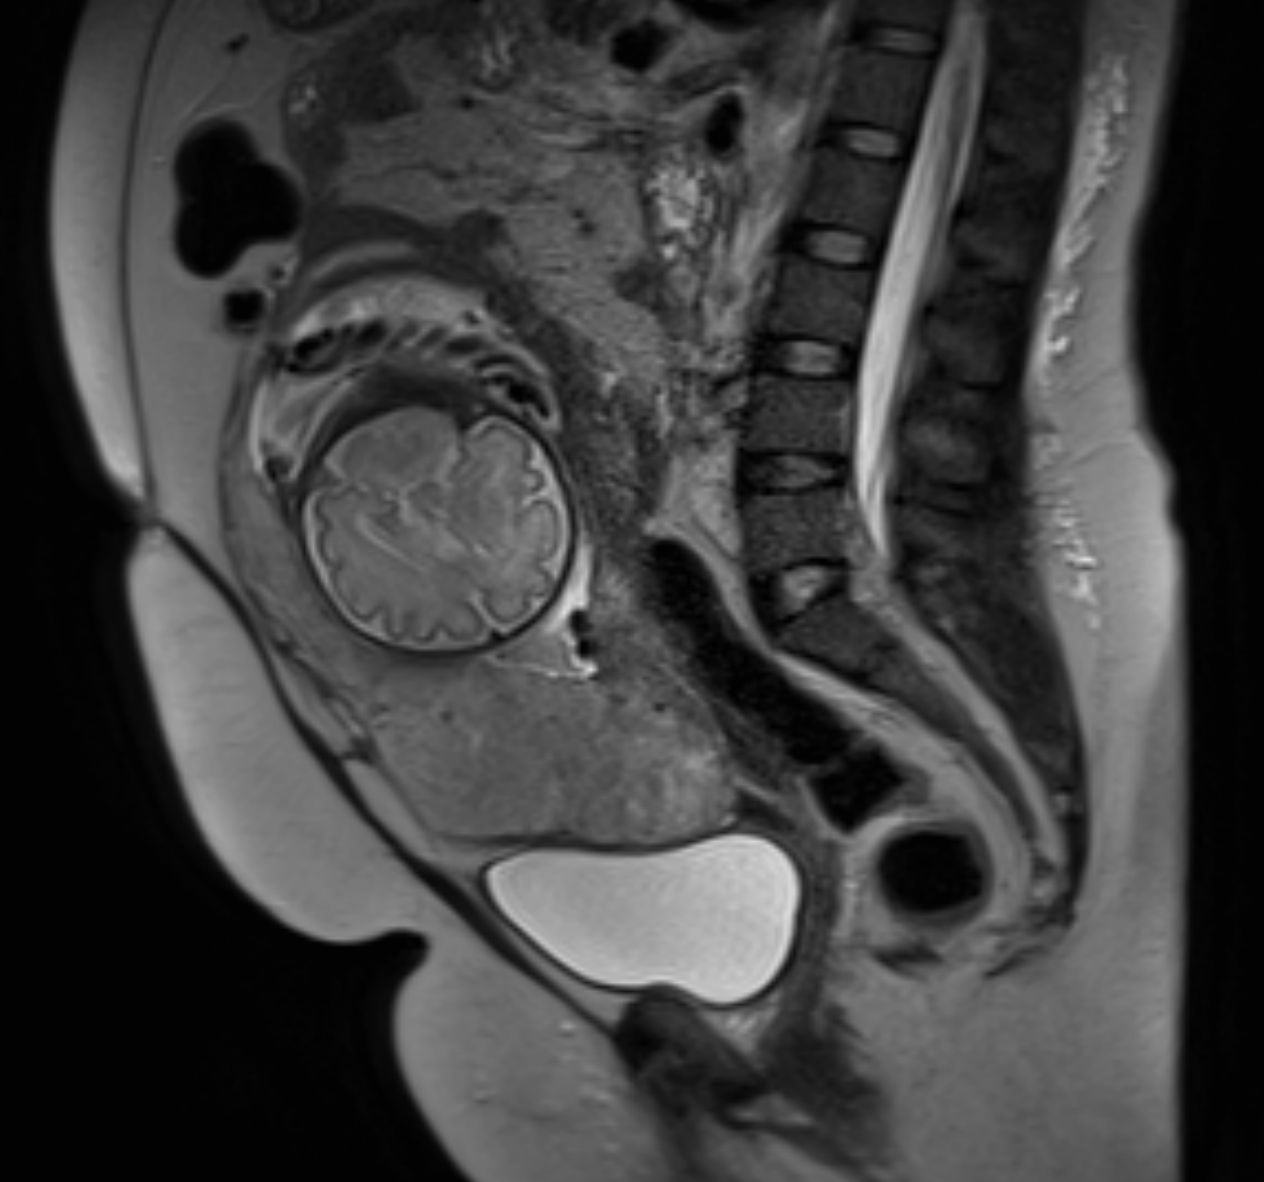

RM_5oANO

Ressonância magnética da pelve (plano sagital). Observa-se volumosa lesão expansiva cervical, heterogênea, com restrição à difusão e realce pós-contraste, medindo aproximadamente 7,7 cm. A lesão se exterioriza para o canal vaginal, com obliteração dos fórnices, e apresenta perda do anel estromal cervical com invasão parametrial bilateral. Achados compatíveis com neoplasia de colo uterino localmente avançada.